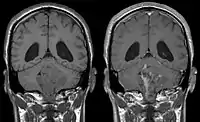

Ependymomas make up about 5% of adult intracranial gliomas and up to 10% of childhood tumors of the central nervous system (CNS). Their occurrence seems to peak at age 5 years and then again at age 35. They develop from cells that line both the hollow cavities of the brain and the canal containing the spinal cord, but they usually arise from the floor of the fourth ventricle, situated in the lower back portion of the brain, where they may produce headache, nausea and vomiting by obstructing the flow of cerebrospinal fluid. This obstruction may also cause hydrocephalus. They may also arise in the spinal cord, conus medullaris and supratentorial locations.[6] Other symptoms can include (but are not limited to): loss of appetite, difficulty sleeping, temporary inability to distinguish colors, uncontrollable twitching, seeing vertical or horizontal lines when in bright light, and temporary memory loss. It should be remembered that these symptoms also are prevalent in many other illnesses not associated with ependymoma.

Although some ependymomas are of a more anaplastic and malignant type, most of them are not anaplastic. Well-differentiated ependymomas are usually treated with surgery. For other ependymomas, total surgical removal is the preferred treatment in addition to radiation therapy. The malignant (anaplastic) varieties of this tumor, malignant ependymoma and the ependymoblastoma, are treated similarly to medulloblastoma but the prognosis is much less favorable. Malignant ependymomas may be treated with a combination of radiation therapy and chemotherapy. Ependymoblastomas, which occur in infants and children younger than 5 years of age, may spread through the cerebrospinal fluid and usually require radiation therapy. The subependymoma, a variant of the ependymoma, is apt to arise in the fourth ventricle but may occur in the septum pellucidum and the cervical spinal cord. It usually affects people over 40 years of age and more often affects men than women.[9]